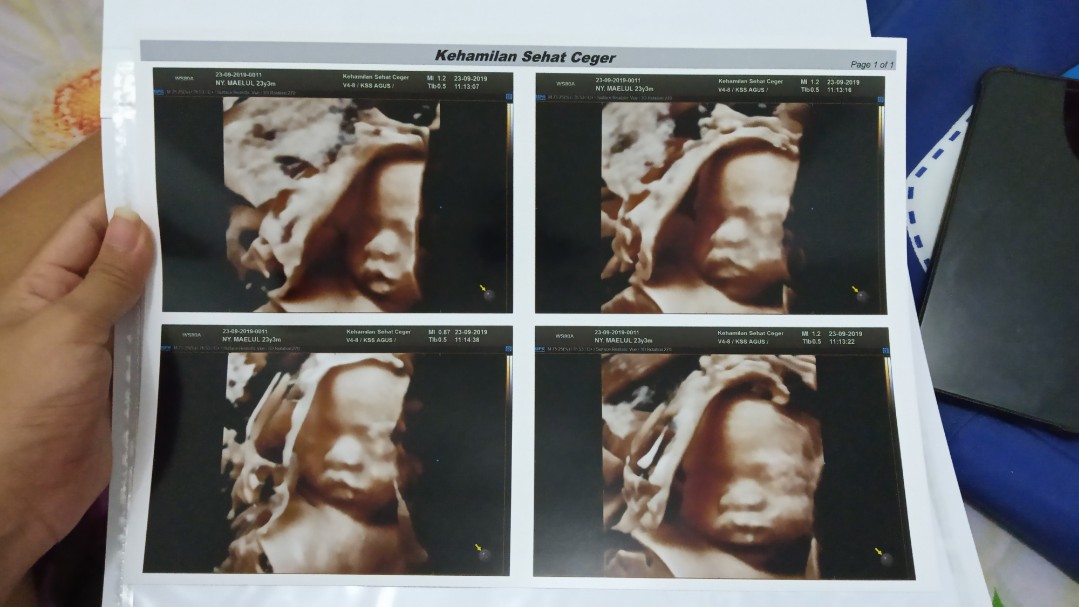

kira kira kalo usg 4d di uk 23w sudah keliatan sempurna belum ya bun anggota tubuhnya.. niatnya pengen usg 4d pas 23w soalnya usg 2d gak jelas